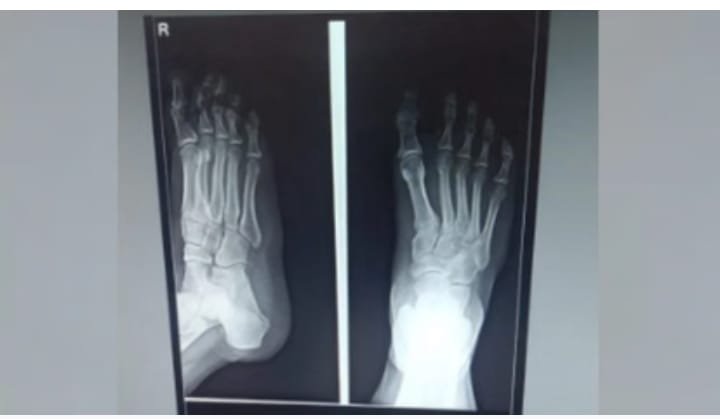

अस्पताल में एआई से एक्सरे रिपोर्ट तैयार की जा रही है। ऐसा करने वाला ये राजधानी का पहला सरकारी अस्पताल बन गया है।

स्वास्थ्य सेवाओं को अत्याधुनिक बनाने की दिशा में ठाकुरगंज संयुक्त चिकित्सालय ने बड़ी उपलब्धि हासिल की है। यह जिले का पहला सरकारी अस्पताल बन गया है, जहां आर्टिफिशियल इंटेलिजेंस (एआई) आधारित मरीजों की रिपोर्टिंग शुरू की गई है। अब अस्पताल के रेडियोलॉजी विभाग में एआई टूल की मदद से मात्र 8 से 10 सेकंड में एक्सरे रिपोर्ट तैयार की जा रही है।300 बेड की क्षमता वाले इस अस्पताल में रोजाना 1000 से 1500 मरीज ओपीडी में आते हैं, जिनमें से औसतन 50-60 मरीजों का एक्सरे होता है। लंबे समय से रेडियोलॉजिस्ट न होने के कारण एक्सरे रिपोर्ट तैयार करने में अड़चन आ रही थी। यह समस्या देख अस्पताल प्रशासन ने एआई की मदद लेने का निर्णय लिया।

सीएमएस डॉ. एसपी सिंह ने बताया कि एआई टूल फॉर एक्सरे की रिपोर्ट बेहद सटीक आ रही है। यह न सिर्फ तेज है, बल्कि टेक्नीशियन इस टूल की मदद से आठ से दस सेकंड में डिजिटल रिपोर्ट भी दे रहा है।